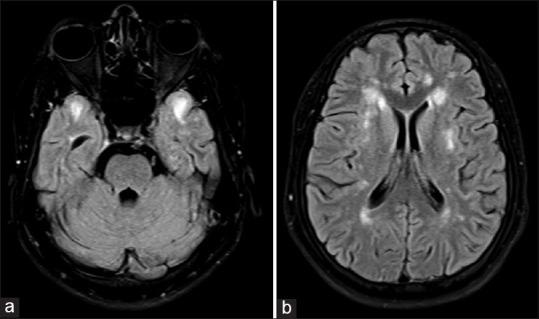

'Raisin bread sign' feature of pontine autosomal dominant microangiopathy and leukoencephalopathy.

Brain Commun. 2023 Oct 22;5(6):fcad281. doi: 10.1093/braincomms/fcad281. eCollection 2023.